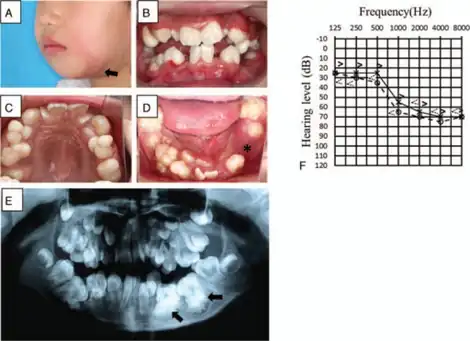

Otodental syndrome, also known as otodental dysplasia, is an exceptionally rare disease that is distinguished by a specific phenotype known as globodontia, that in rare cases can be associated with eye coloboma and high frequency hearing loss. Globodontia is an abnormal condition that can occur in both the primary and secondary dentition, except for the incisors which are normal in shape and size.[1][2][3] This is demonstrated by significant enlargement of the canine and molar teeth.[1] The premolars are either reduced in size or are absent.[3] In some cases, the defects affecting the teeth, eye and ear can be either individual or combined.[4] When these conditions are combined with eye coloboma, the condition is also known as oculo-otodental syndrome. The first known case of otodental syndrome was found in Hungary in a mother and her son by Denes and Csiba in 1969.[5] Prevalence is less than 1 out of every 1 million individuals.[2] The cause of otodental syndrome is considered to be genetic. It is an autosomal dominant inheritance and is variable in its expressivity.[6] Haploinsufficiency in the fibroblast growth factor 3 (FGF3) gene (11q13) has been reported in patients with otodental syndrome and is thought to cause the phenotype.[2] Both males and females are equally affected. Individuals diagnosed with otodental syndrome can be of any age; age is not a relevant factor. Currently there are no specific genetic treatments for otodental syndrome. Dental and orthodontic management are the recommended course of action.[1]

- Globodontia – an abnormal condition that can occur in both primary and secondary tooth development, in which the molars and canines are greatly enlarged. It refers to the enlarged bulbous fused malformed posterior teeth with almost no discernible cusps or grooves.[1] The molars are known to have a rounded globe-like shape. Can attribute to pain.

- Sensorineural hearing loss (SNHL) – also known as nerve related hearing loss, is a form of hearing loss associated with complications within the inner ear.[7]

- Taurodontism – known as a condition in which the body of a tooth is enlarged at the expense of the roots. This results in an enlarged pulp chamber, lack of proper bonding at the cementoenamel junction, and can cause the pulpal floor to be displaced towards the root.[8] Discomfort and pain are usually associated with these characteristics.

Diagnosis of otodental syndrome was established using clinical, histopathological and audiometric methodologies.[4] In normal individuals, by the age of 2-3, radiograph images should depict any signs of premolar development. A formal diagnosis of no premolar growth can be done by age 6 in order to check for signs of otodental syndrome.[3] Sensorineural hearing loss can be another measure for proper diagnosis as well as checking for ocular coloboma. The latter is usually noticed at an around birth.